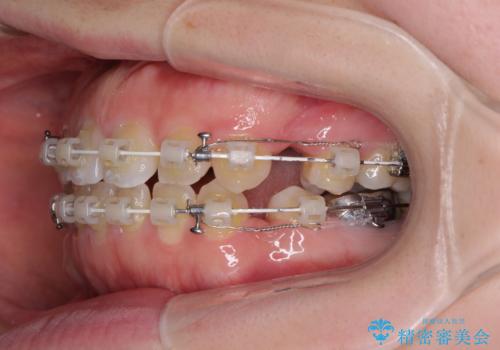

- 矯正装置

- 審美装置

- 口元の膨らみが気になるとのことで来院された患者様です。

非抜歯で口元の突出感を少し改善させる治療も提案しましたが、最大限口元を引っ込めたいとのことでした。

上下左右第一小臼歯4本を抜歯し、ワイヤー装置により矯正治療を行うこととしました。

治療は順調に進み、予定された期間で終了することができました。

装置除去後には、スッキリとした口元となり、大変満足していただきました。